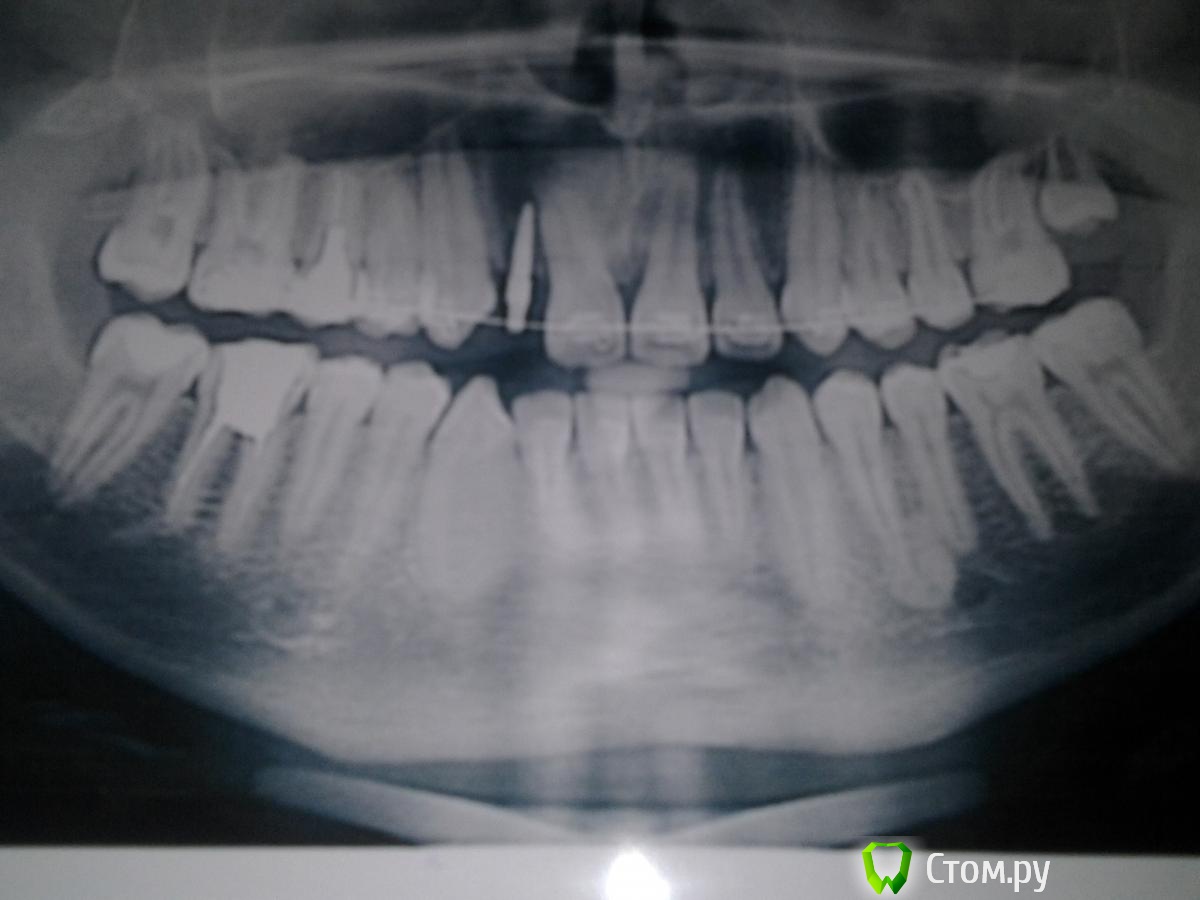

nurseit Опубликовано 13 января, 2014 Поделиться Опубликовано 13 января, 2014 Доброго времени суток, Уважаемые коллеги. 1 снимок сделан 30.03.2012. Второй 09.01.2014. Разница, почти 2 года. Интересует область 34,35 корней зубов. 1. Что это?2. Какова тактика? Ссылка на комментарий

Afffinity Опубликовано 13 января, 2014 Поделиться Опубликовано 13 января, 2014 В области 34 гиперцементоз, а в области 35 похоже на foramen mentale. 1 Ссылка на комментарий

zzkz Опубликовано 14 января, 2014 Поделиться Опубликовано 14 января, 2014 Доброго времени суток, Уважаемые коллеги. 1 снимок сделан 30.03.2012.Второй 09.01.2014. Разница, почти 2 года. Интересует область 34,35 корней зубов. 1. Что это?2. Какова тактика?в динамике вроде норм. ничего не делать/наблюдать Ссылка на комментарий